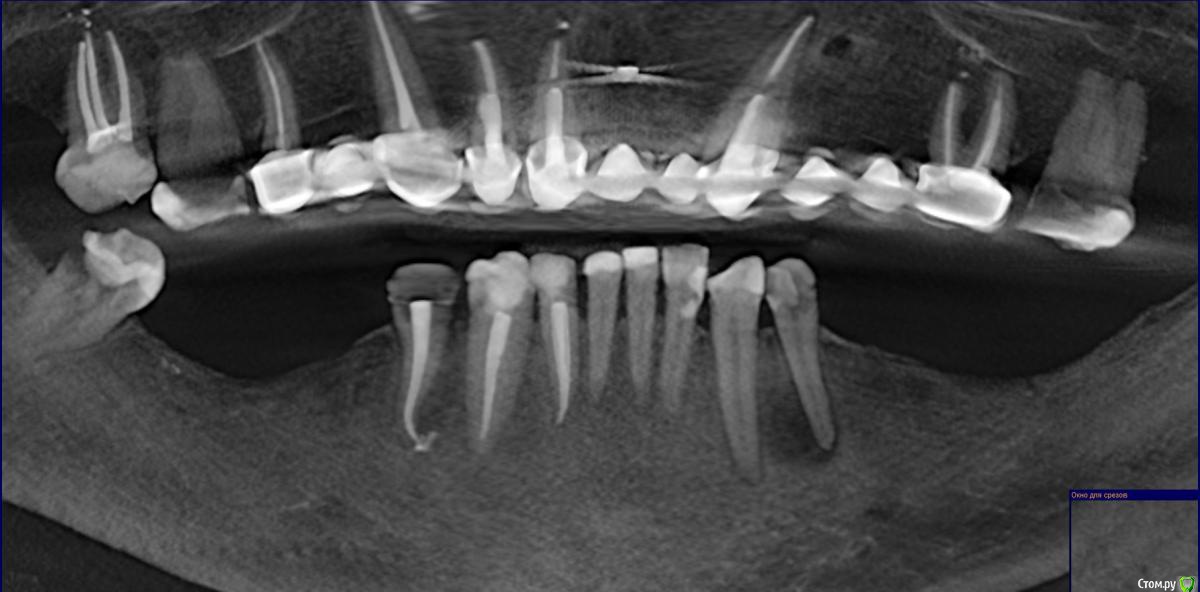

Прошу совета по плану остеопластики с дальнейшей имплантацией (на нижней челюсти).

53 года. Необходимо протезирование нижней челюсти.

Все врачи говорят о недостатке костной ткани (3мм).

Все говорят о необходимости удалить 4-ку слева (так как большая киста, зуб спасти невозможно). Вопросы по поводу дальнейших действий и общей стратегии протезирования.

4-ку слева (с кистой) удаляем, 4 справа оставляем (там воспалена десна, но ортопед говорит, это потому что скол идет по десне, надо поставить временную пломбу). Ортопед снимки смотреть не стала, смотрел хирург, он тоже считает что правую 4-ку можно сохранить.

Слева и справа делаем расщепление гребня, потом слева ставим 3 импланта, справа - два.  Передние зубы не депульпируем (так как они маленькие (сильно сточенные) и их надо не обтачивать, а наращивать., на них коронки. Восстанавливаем зубной ряд по 7-ки включительно.

Снимки месячной давности (8-ка уже удалена). Прикус на этом снимке не видно, нижняя челюсть смещена внутрь по отношению к верхней (не знаю, важно ли это)

я попыталась сделать принтскрины с 3D, но, к сожалению, не очень понимаю, какие снимки (углы, ракурсы) нужны, может быть сделала не то и не так, сорри. Понимаю, что скачивать 3D времени у большинства нет.

post-48869-0-20530400-1472582105_thumb.jpg

post-48869-0-99232900-1472582231_thumb.jpg

post-48869-0-09101500-1472582237_thumb.jpg